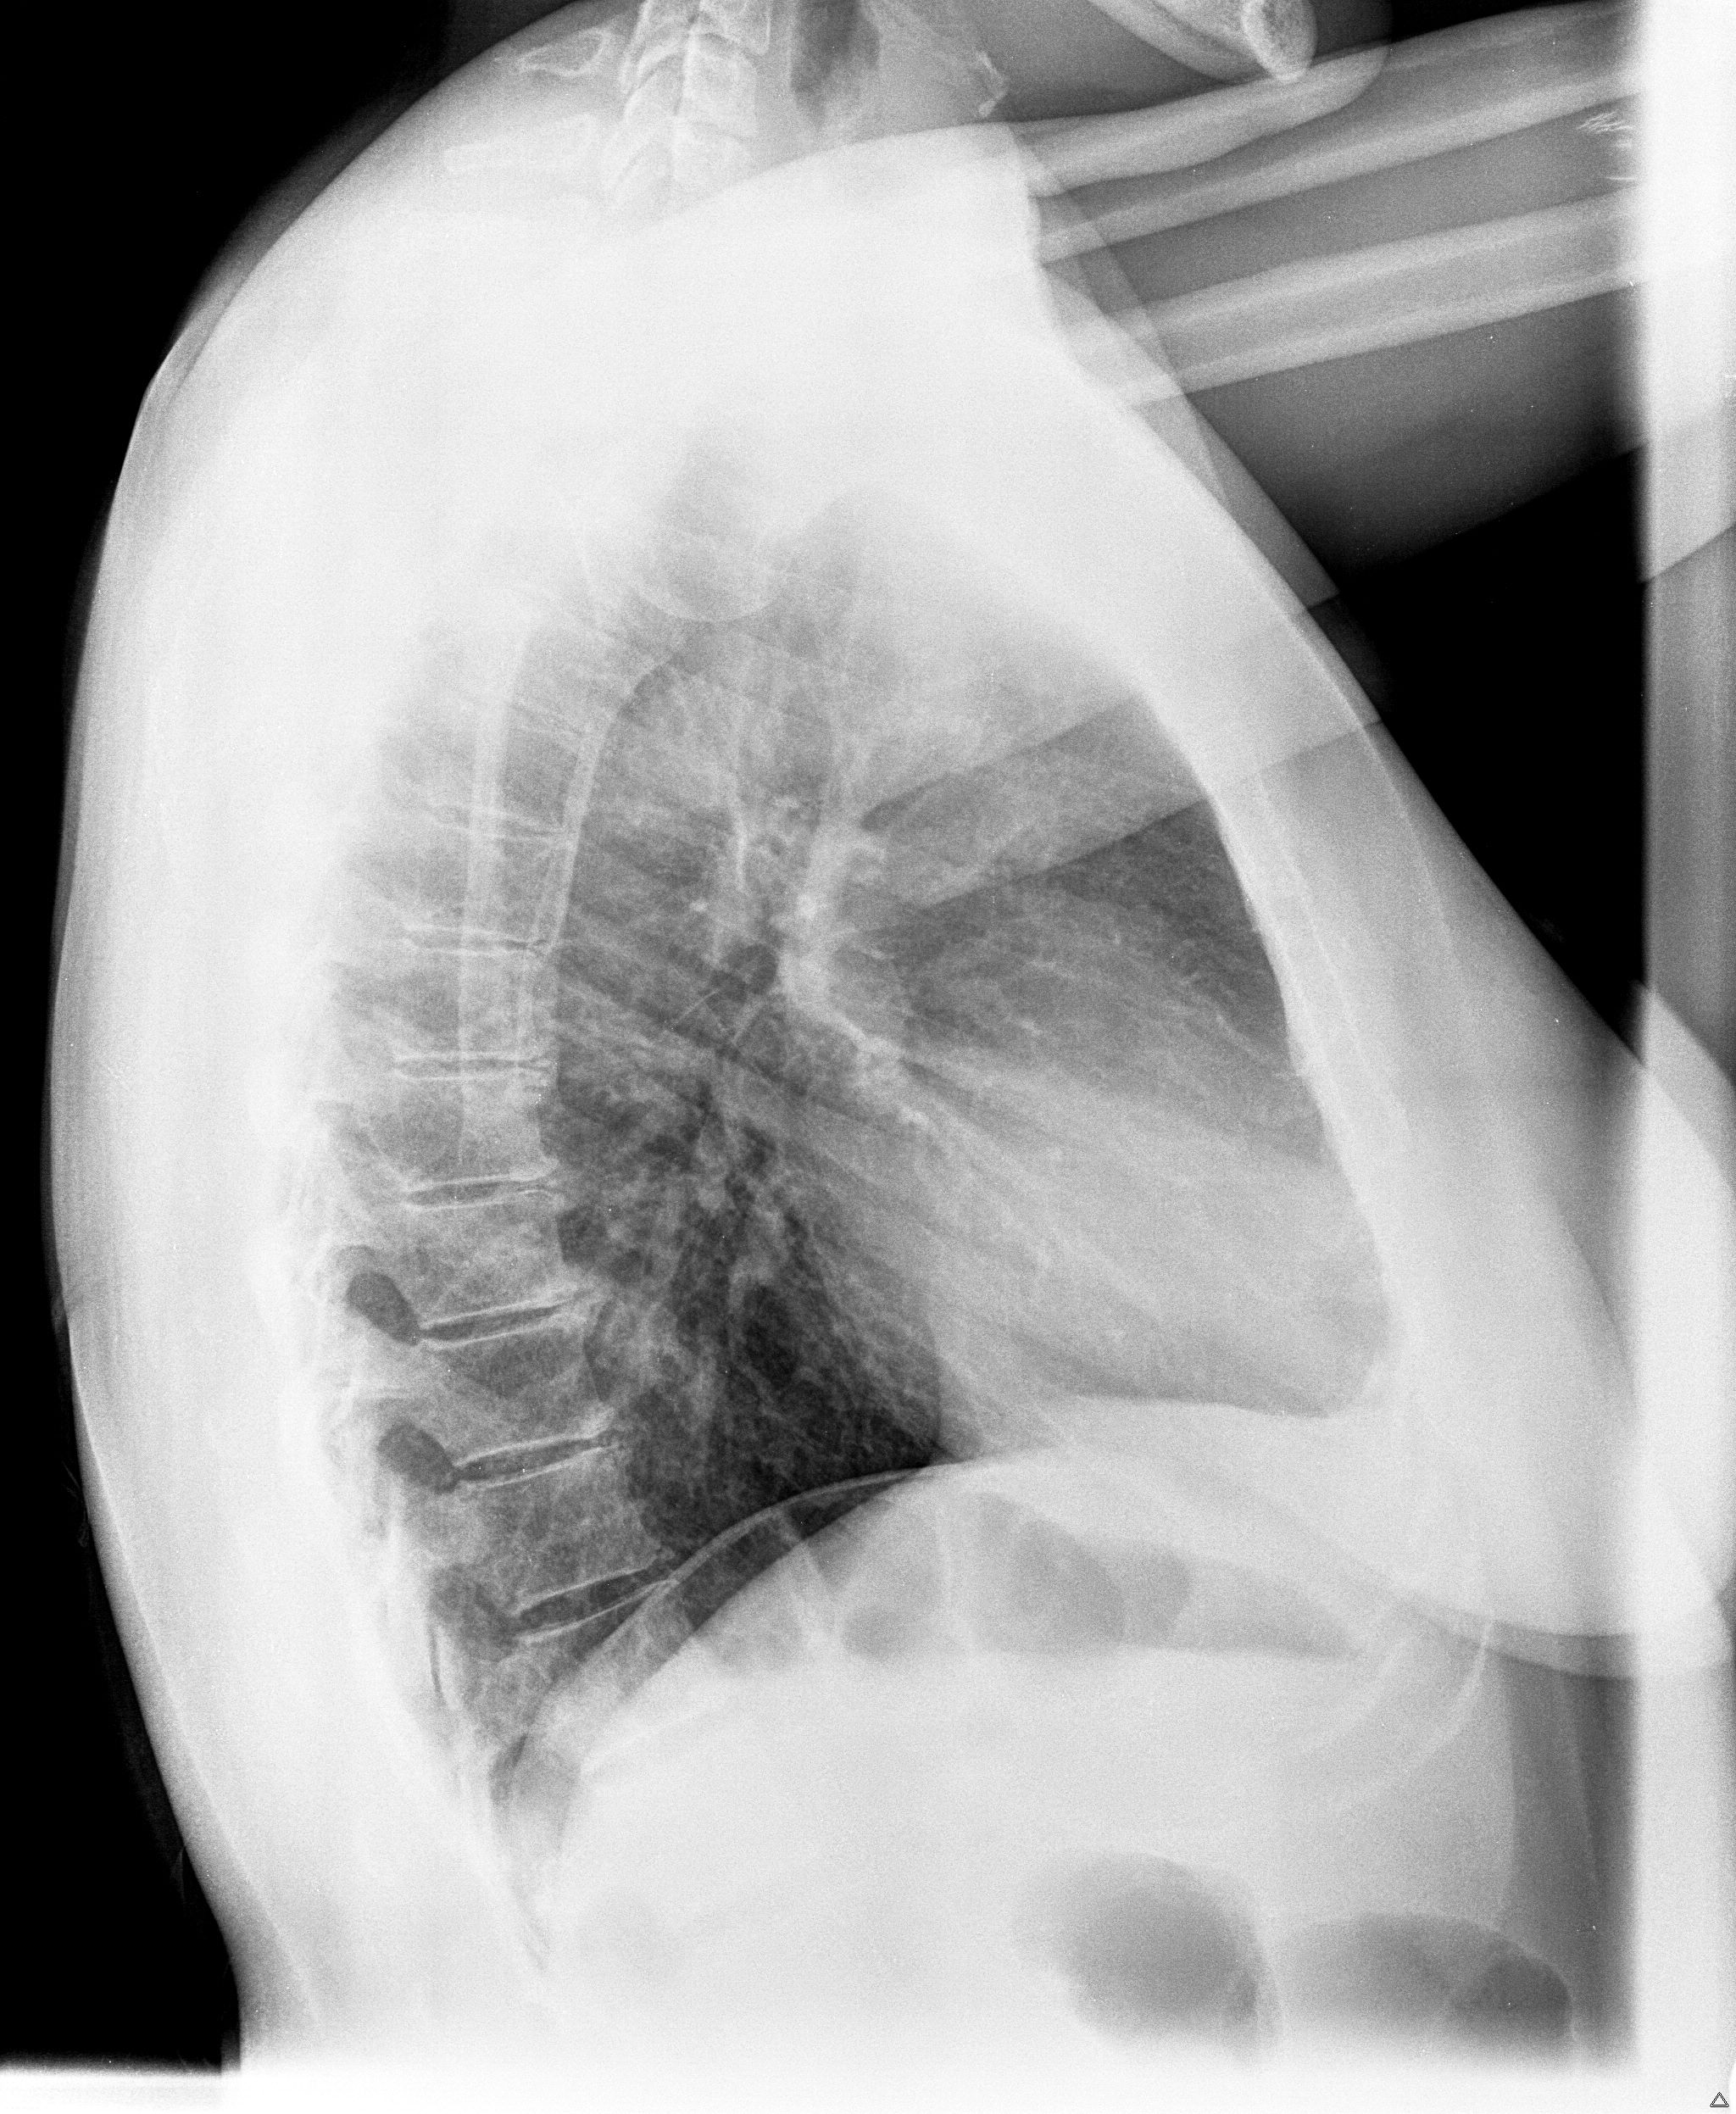

buongiorno dopo tutta una serie di esami effettuati nel corso di quest anno (ecocuore, gastroscopia, ecografia addome... tutti negativi) per capire l origine di questo mio fastidio ieri ho fatto i raggi al torace premetto che sono una fumatrice da 10 sigarette al di con un passato da fumo passivo non indifferente...vorrei capire se effettivamente ho qualcosa per cui preoccuparmi specifico che ho 39 anni

00001.jpg

[ 694.3 KiB | Osservato 4171 volte ]